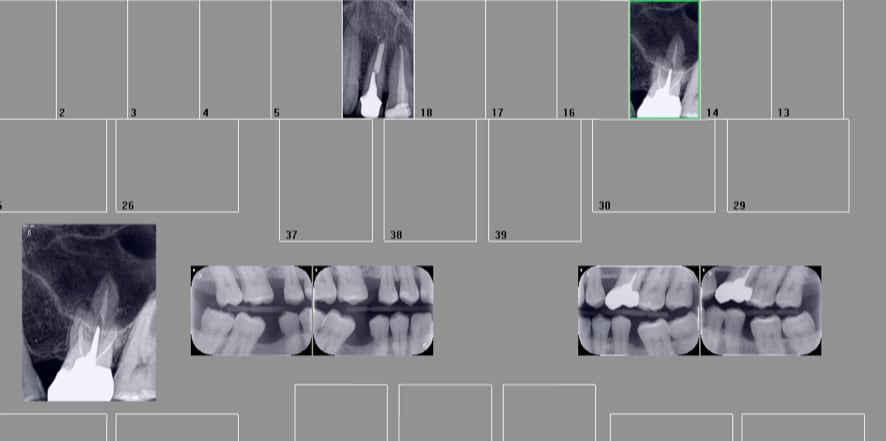

Capture d écran 2017 07 19 11.40 - Eugenol

Capture d écran 2017 07 19 11.39 - Eugenol